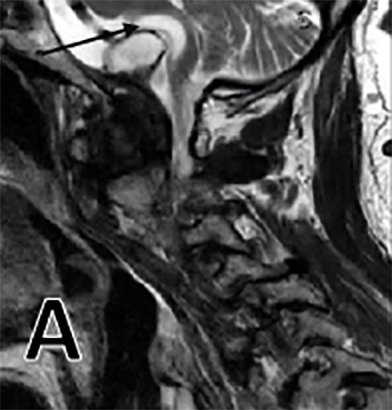

After his work-up was completed, the patient was found to have large odontoid pannus causing compression at the cranial cervical junction. We also noted a cyst associated with this pannus causing significant mass effect on the medulla (Figure 1 E). On MRI, this produced a T2 hyperintense signal at the medulla consistent with encephalomalacia, or medullary atrophy (Figure 1 A). The patient also had diffuse spondylosis, or degeneration, of the cervical spine along with central stenosis at the C4-5 and C5-6 level (Figure 1 C). Both an MRI of brain and CT angiogram were obtained and failed to reveal any other pathology. The posterior odontoid mass was found to be due to his rheumatoid arthritis.

The patient was followed up for two years. There was improvement in his motor weakness symptoms and he was eventually able to ambulate without an assisted device. Radiographic evaluation at the two-year follow-up mark showed marked reduction in the pannus and associated cyst with resolution of T2 hyperintense signal within the medulla (Figures 1 B, F). While there are reports in the surgical literature of smaller-sized pannus causing cervical spinal cord compression, we have been unable to identify any reports of such a large odontoid pannus with associated cyst and medullary compression.8